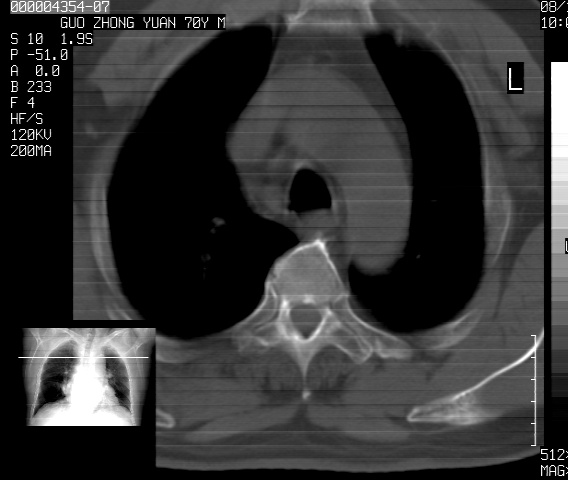

以下是引用sdzyy在2008-12-1 11:49:00的发言:[br]图像不全,请上传,右下肺炎症可能性大,占位待排.

以下是引用zjzjr在2008-12-1 14:53:00的发言:[br]图像不全,请上传,右下肺炎症可能性大,占位待排.心影增大,建议进一步检查.